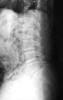

Osteoporosis. Cifosis.